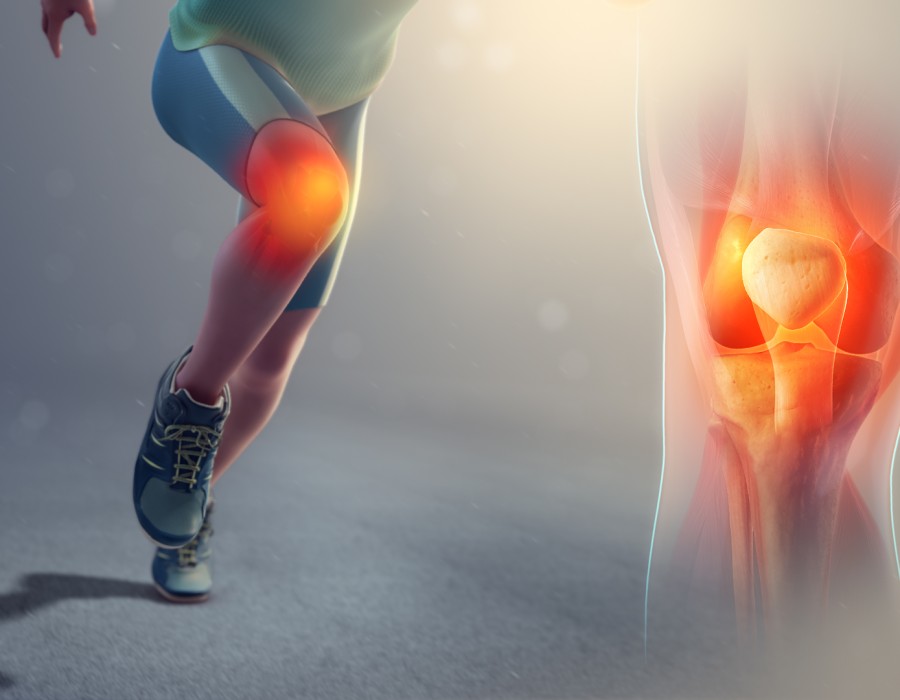

- Tendon and Ligament Tears: Such as ACL (Anterior Cruciate Ligament) tears, which are prevalent in sports like soccer, basketball, and football.

- Surgical Interventions: When necessary, surgeries such as arthroscopy (minimally invasive joint surgery), ligament reconstruction, or fracture fixation may be performed to repair the injury.

- Non-Surgical Treatments: This includes rest, physical therapy, medications, and injections to promote healing and reduce pain and inflammation.

- Rehabilitation Programs: Customized rehabilitation plans are crucial for athletes to regain strength, flexibility, and function post-injury.